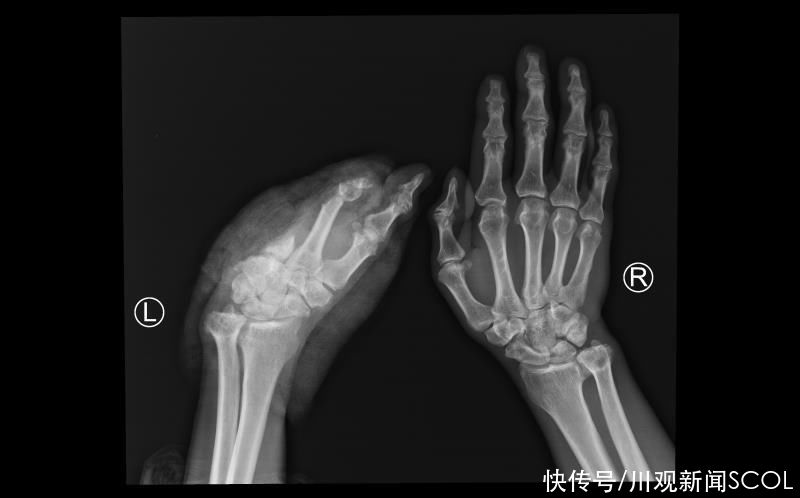

55岁的患者是西藏昌都人,8月9日下午,因车祸伤导致左手掌完全离断,因当地医院无再植医疗条件,经过初步处理后,采用疫苗冷链箱保存离断肢体,患者搭乘飞机于8月10日下午到四川省人民医院骨科急诊入院。

一般断肢再植的最佳时机是伤后6-8小时,而该患者来院时离断肢体缺血时间已经超过24小时,且车祸伤导致的残端不规则,再植手术难度大,术后出现并发症的风险高。

【 川观|四川省人民医院完成超长时间缺血断掌再植术】骨科肖成伟博士团队请示骨科胡豇主任,开展科内讨论后,决定冒着风险,做一次尝试性再植,给患者一次机会。经过积极的术前准备,在麻醉手术中心等相关科室的支持下,肖成伟博士团队很快开始了急诊再植手术。经过显微镜下长达6个半小时的奋战,一共吻合重建了3根动脉,6根静脉,5根神经,14根肌腱。8月11日凌晨2点,患者离断肢体恢复血供,再植手术获得初步成功。

术后一周,再植肢体安全度过了术后发生血管危象的可能。目前,再植肢体完全存活,其他功能也在逐步恢复中。据主刀医生介绍,康复后,患者虽然不能进行精细动作,但一般的生活自理是没问题的。